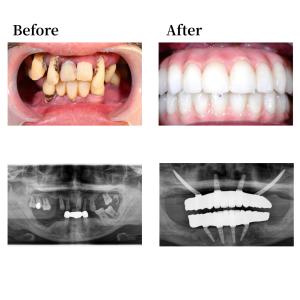

背景

歯を失ったことで「マスクがないと喋れない」という深い悩みを抱え、相談まで5年もの歳月を要しましたが、ネット検索で当院HPを見つけ受診に至りました。既往歴や内服薬はありませんが、喫煙(20歳から1日20本)と飲酒(1日350ml×8本)の習慣があります。口腔内の診査後、理事長より上顎に2本のザイゴマインプラントを併用したオールオン4計画を提案。1日で歯が入り、会話や食事の自信を取り戻せる点に強い魅力を感じられ、手術を決断されました。

インプラント詳細

上顎骨の形状を整え、12,22の位置にオールオン4インプラントを0度垂直埋入。15, 25 の位置にザイゴマインプラントを45度傾斜埋入。下顎は残存歯を抜歯後に形状を整え、45, 42, 32, 35の位置にそれぞれオールオン4インプラントを埋入。 42, 32の位置に、0度垂直埋入、45, 35の位置に17度傾斜埋入。その後、マルチユニットアバットメントで角度補正を行い、プロビジョナルレストレーション(審美的な仮歯)を装着した。

上部構造詳細

上下顎はモノリシックジルコニアで構成された、フルジルコニアブリッジでファイナルレストレーションとした。焼成されたジルコニアはステインテクニックで着色した。シェードカラーはA1。